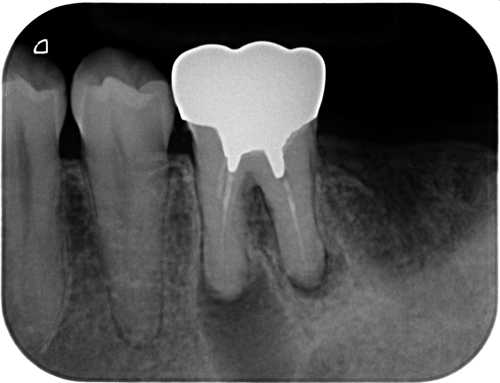

レントゲン上では、確かに大きな透過像が確認できます。一般的には、この大きさだけで「もうダメですね」と判断されることも少なくありません。

今回の歯も、既に根管治療は行われていました。しかし感染源が取り切れていない状態でした。こういうケースでは、どれだけ時間が経っても、どれだけ薬を入れても治ることはありません。再治療では、根管内の再評価と見落とされていた部分の処理を丁寧に行いました。特別なことをしたわけではありません。原因を取り除いただけです。

術後3ヶ月で透過像の改善が確認できました。